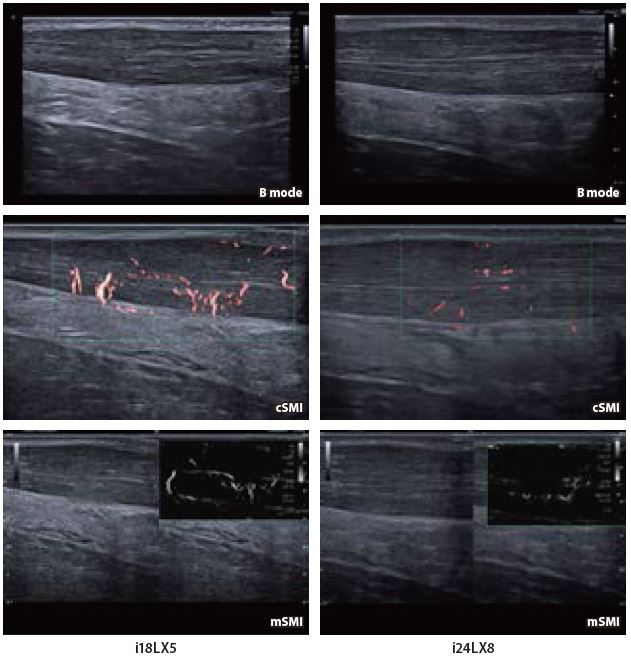

Випадок 2: сухожилля надвиросткового м'яза та субакроміальний субдельтоподібний бурсит

i18LX5 демонструє детальні структури з хорошим проникненням, що дозволяє оператору швидко провести це планове обстеження з високою діагностичною достовірністю. i24LX8 демонструє значно підвищену деталізацію тканин у ближньому полі та достатнє проникнення через все сухожилля надвиросткового м'яза, що дозволяє проводити клінічну діагностику. Ці парні зображення демонструють можливості як i18LX5, так і адекватну глибину проникнення надвисокочастотного датчика i24LX8, що дозволяє використовувати його для загальної візуалізації опорно-рухового апарату.

Мал. 4.

Обидва лінійні датчики i-серії демонструють хорошу деталізацію потовщеного ахіллового сухожилля, а також наявність неоваскуляризації, що підтверджує діагноз. Однак при використанні надвисокочастотного датчика тонке веретеноподібне потовщення і структура сухожилля окреслюються краще і з більшою деталізацією, хоча спостерігається незначне послаблення допплерівського сигналу.

Мал. 6.